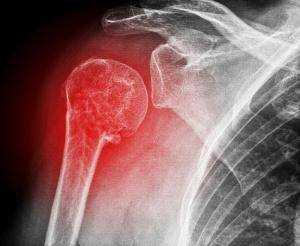

Рентген в двух проекциях (прямой и осевой) довольно чётко может показать отклонение текущего состояния плечевого сустава от нормы. На снимках можно увидеть, насколько смещена головка плечевой кости, каково направление её смещения, а также наличие переломов костей (если они есть). С помощью рентгена можно определить тип вывиха и предположить развитие возможных осложнений. Не допускается вправлять вывих без предварительного проведения рентгена.

Перелом шейки плечевой кости, боковой части лопатки или ключицы

Все кости на рентгене отображаются в виде плотных белых образований. Переломы костей, а также трещины на них выглядят на снимках как тёмные полосы, расположенные в различных направлениях и имеющие различную локализацию и размер. Фото-рентген плечевого сустава позволяет обнаружить наличие переломов плечевой кости, ключицы и лопатки. Снимок нужен для того, чтобы определить сложность перелома, увидеть, как расположены осколки костей (если имеет место раздробление).